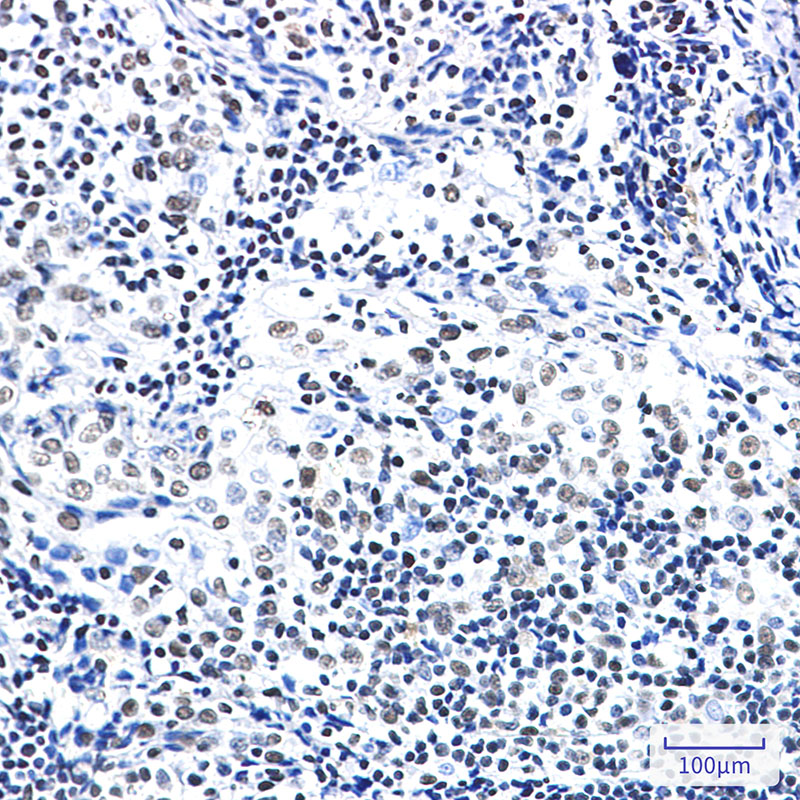

- Immunohistochemistry analysis of paraffin-embedded Human tonsil using ZBTB7A antibody.High-pressure and temperature Sodium Citrate pH 6.0 was used for antigen retrieval.